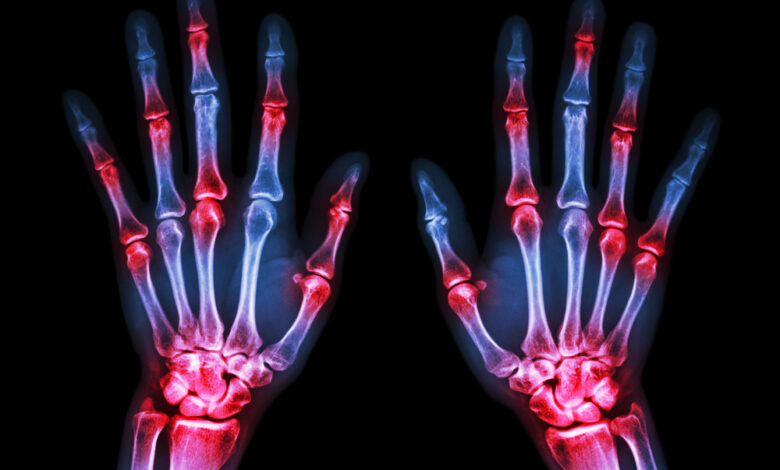

Артрит локтевого сустава — это воспалительное заболевание, которое может привести к боли, отечности и ограничению движения в локте. Важно знать основные симптомы этого состояния:

- Боль при движении локтя.

- Отек и покраснение кожи в области локтя.

- Теплота вокруг сустава.